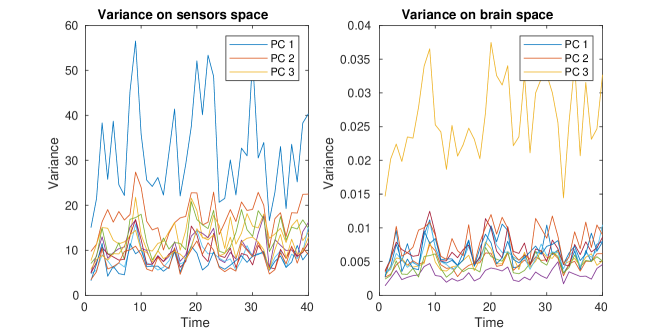

In Figure 12, we show the plot of variances associated with each time segment, describing the variation in time of the PC covariance functions, hence the variation in interconnectivity. The variance can be either defined on the sensors space, by normalizing the PC covariance functions , with the forward operator, or on the brain space, by normalizing the PC covariance functions on the brain space . Due to the presence of invisible dipoles, which are dipoles that display zero magnetic field on the sensors space, the two norms can be quite different, leading to different average variances for each PC covariance function. Due to the high sensitivity of the source space variances on the choice of the regularization parameter, we focus on the estimated variances on the sensors space.

We have also applied our model to the covariances obtained by subdividing the MEG session in segments. As expected the PC covariance functions, shown in Figure B.5 are very similar. However, the variances, in Figure B.4, show higher variability in time, which can be partially explained by the fact that shorter time segments lead to covariance estimates that have higher variability.

The second part of the analysis focuses on applying the proposed methodology to a multi-subject setting. Specifically, different subjects are considered. For each subject, the 6 minutes scan is used to compute a covariance matrix, resulting in covariance matrices . The template geometry in Figure 10 is used as a model of the brain space. Algorithm 2 is then applied to find the PC covariance functions on the template brain, associated with . We run the algorithm for iterations, and choose the regularizing parameter to be by inspecting the L-curve plot in the right panel of Figure B.2. The results for are shown in the appendices. The energy maps of the estimated functions , and and the associated first three covariance functions , and , are shown in Figure 13. High intensity areas, in yellow, indicate which areas present high average connectivity. In Figure 14, we show the subject-specific associated variances, both in the sensors space and the brain space.

In Figure B.3-B.4 we show respectively the plots of the estimated PC covariance functions and associated variances from the dynamic functional connectivity study on segments with regularization parameter .

In Figure B.5-B.6 we show the estimated PC covariance functions and associated variances from the dynamic functional connectivity study on time segments with regularization parameter .